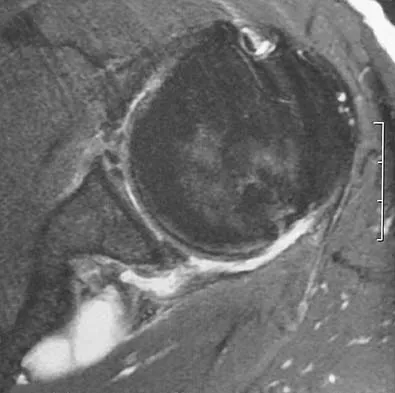

A 35-year-old woman who is a recreational runner reports posterior knee pain and tightness in the knee with flexion during running. She denies any history of trauma. Examination reveals normal patellar glide and tilt and no patellar apprehension. Range of motion is 5 degrees to 120 degrees, and quadriceps function and knee ligamentous examination are normal. Radiographs are normal. An MRI scan is shown in Figure 18. What is the most likely diagnosis?

Explanation